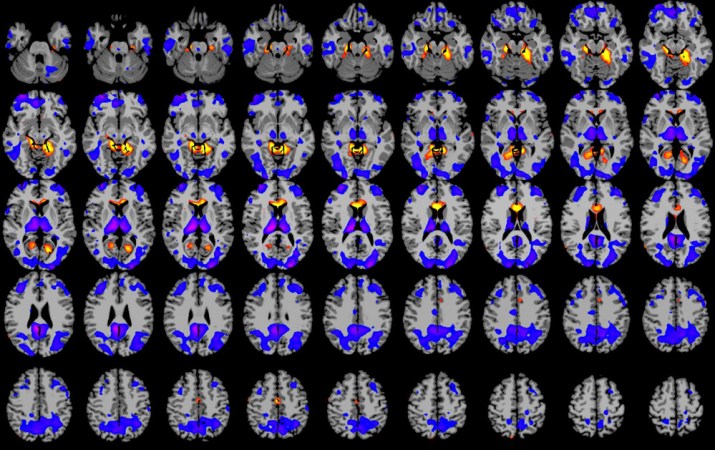

To understand how various drugs work in the brain, Brown and his team at Massachusetts General Hospital put a group of healthy participants under general anesthesia. Instead of going into surgery, these volunteers went inside a machine that uses a powerful magnetic field to show researchers which brain regions are active. (This machine performs what’s called functional magnetic resonance imaging, or fMRI.)

The scientists wanted to see which brain areas the drugs turn on. Nicholas Schiff, a doctor at Weill Cornell Medical College in New York City, reviewed these studies. He says the data show that these medications slow the activity of brain cells, or neurons, and alter their patterns of communication.

Two key parts of the brain change their conversations with each other. They are the cerebral cortex and the thalamus. The cerebral cortex is the wrinkled layer of nerve cells that covers the surface of a part of the brain called the cerebrum. It plays a major role in attention and information processing. The thalamus is a ball of tissue at the center of the brain. It acts as a traffic cop to direct the flow of sensory information into the brain.

Under normal circumstances, these two regions continuously pass signals between each other to make sense of what a person sees, hears and feels. When these areas stop communicating, signals from the outside world can’t get through. That’s why the sights and sounds of the operating room — even pain — won’t register with a patient.

Instead of looking like sleep, the quiet brain patterns seen during anesthesia resemble those found in coma patients.